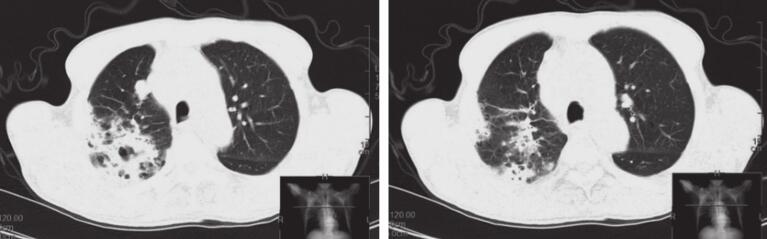

入院后先后给予“亚胺培南西司他汀、左氧氟沙星+万古霉素”抗感染等综合治疗,上述症状无缓解,复查胸部CT示病灶较前增多(图1),遂于2014年11月24日行CT引导下经皮肺穿刺活检术,病理示“机化性肺炎”,调整抗生素为“头孢哌酮舒巴坦”,同时给予“甲泼尼龙”应用后症状逐渐好转,后复查胸部CT示病灶较前明显吸收,但右上肺结节及纵隔多发淋巴结无明显变化。复查癌胚抗原42.96ng/ml,考虑恶性肿瘤可能,于2014年12月10日行TBNA检查,病理提示找见恶性肿瘤细胞,倾向小细胞癌。患者及家属要求出院,告知相关风险,表示理解,后患者再次出现反复发热,最高38.5℃,热型不规则,发热前无寒战,复查胸部CT示右肺结节样病灶较前略增大,提示肺癌在进展。于2014年12月27日行“EP”方案化疗,具体剂量:依托泊苷0.1g d1~3,顺铂30mg d1~3,并继续给予甲泼尼龙片口服,并逐渐减量。患者体温逐渐降至正常,咳嗽、咳痰症状逐渐好转,咯血、胸痛症状消失。

图1 2014年11月15日(A)、2014年12月25日(B)、2015年1月14日(C)CT表现

右肺可见斑片状高密度影,右上肺见结节影。经治疗后右上肺斑片影较前明显吸收,右上肺结节较前增大后又趋于稳定。现仍处于随访中